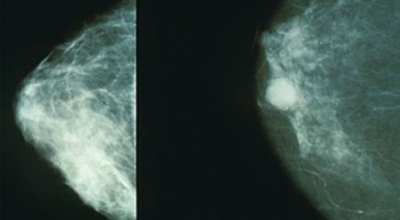

여러 유방암 초기증상들이 있겠지만, 빠른 검사가 필수겠지요. 진단을 위하여 유방촬영술과 초음파를 시행할 수 있다고 해요. 기본으로 시행되는 유방암 검사 중 한가지인 유방촬영술이 있다고 하지만, 한국 여성들은 치밀유방인 경우가 많다고 하지만, 이는 지방조직은 적고 유선조직은 많은 양 있어서 촬영 시에 사진이 하얗게 찍힐 수 있어 혹의 유무를 파악하기가 쉽지 않을 수 있다고 해요.

그리해서 유방암 검사 중 초음파도 병행하게 됩니다. 초음파를 통하여 조직에 생성된 혹의 악성과 양성을 파악하는데 도움을 준다고 해요. 초음파를 진행해도 유방 촬영술 검사는 필요하고, 이유는 미세석회화와 같은 것의 파악은 이 검사로 더욱 잘 관찰될 수 있다고 해요. 이 외 유방암 검사로는 조직검사와 세포침 검사를 통해 병의 상태를 볼 수 있다고 해요.